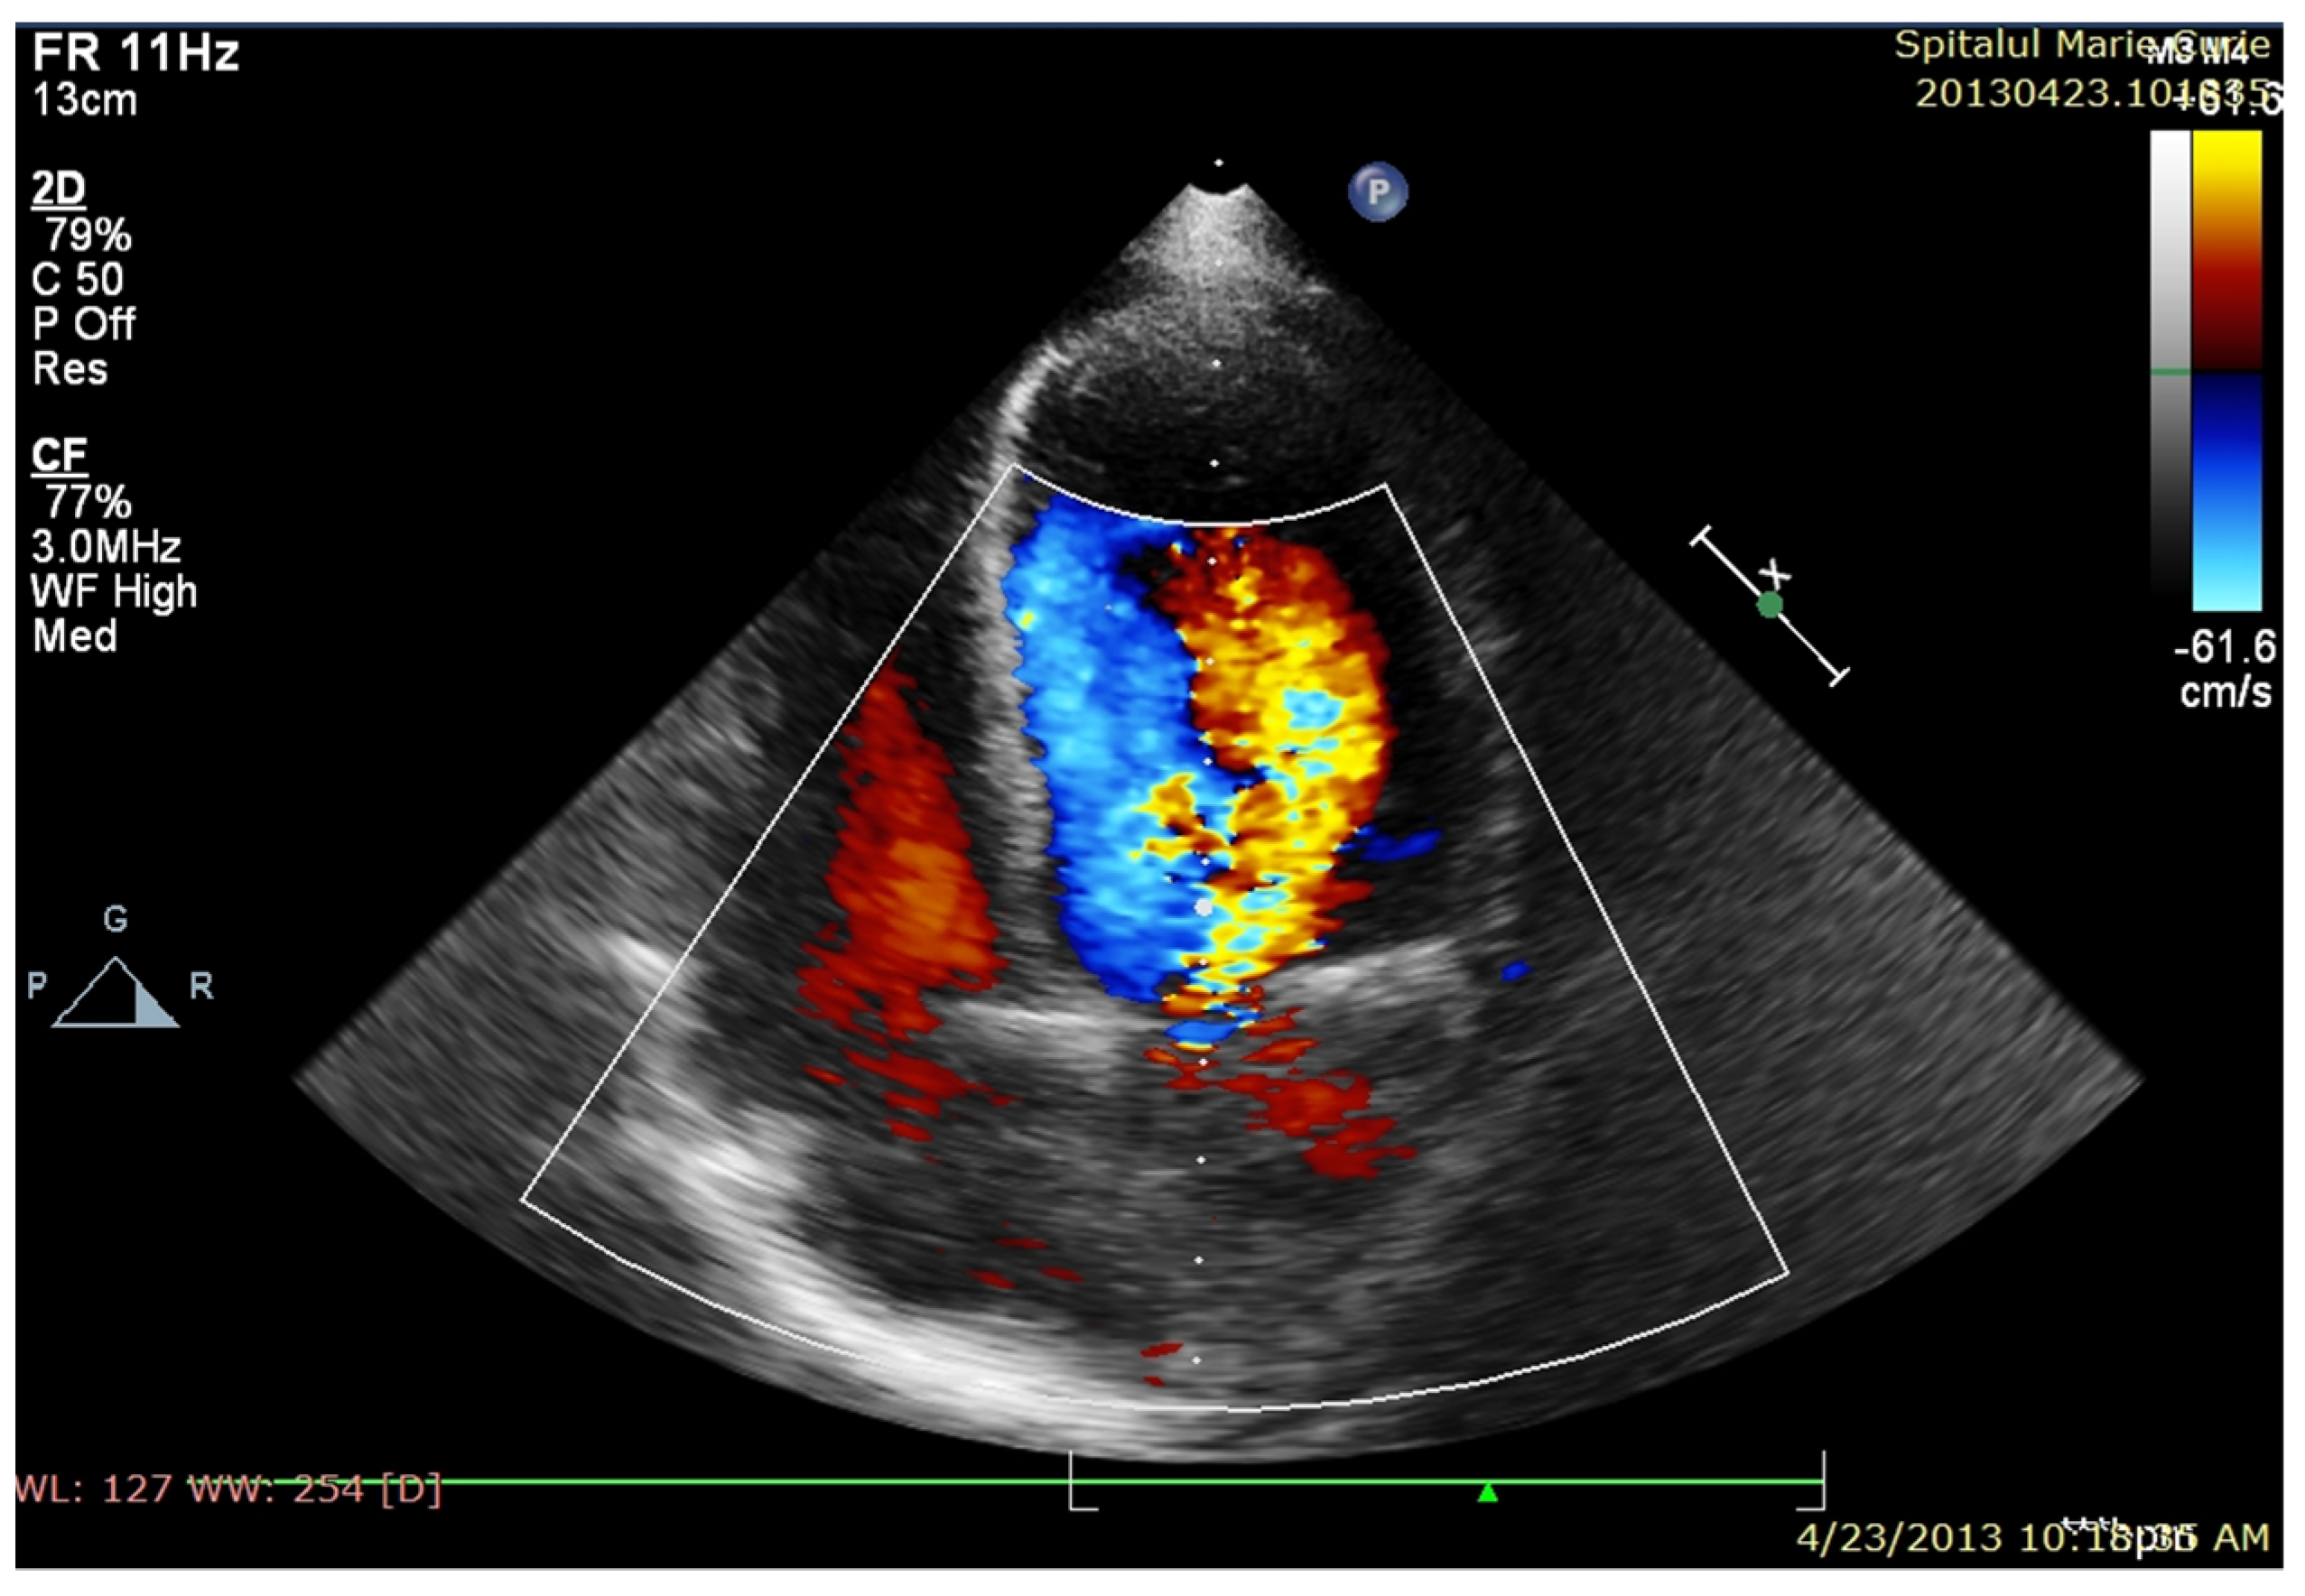

After completing antibiotic therapy (6 weeks), the patient was in a relatively good clinical condition, with reasonable control of hypertension (secondary to aortic coarctation), dyspnea on moderate exertion, an IV/VI-grade systolic murmur in the aortic area, marked diastolic murmur, mild anemia and regular inflammatory tests. Transthoracic echocardiography (Figure 2) revealed moderate aortic valve stenosis, severe aortic regurgitation, severe aortic coarctation, progressive dilatation and decreased LV systolic function (LVEF = 35%). Unexpectedly, muscle enzymes increased over the next two weeks to a high serum level, especially CK, whose serum level range was 3800–8500 Ui/L. During the first phase of endocarditis evolution, high cardiac, liver and muscle enzyme levels were interpreted in the context of LV systolic dysfunction (secondary to severe acute aortic insufficiency and possible coronary flow steal) associated with a potential adverse reaction of cytolysis-causing drugs. However, the increasing trend of these blood tests, along with some motor features, such as Gowers’ sign and staggering gait, required a neurological examination, raising the suspicion of hereditary muscular dystrophy. Multiplex-ligation-dependent probe amplification (MLPA) was used as the diagnostic test (from a peripheral blood sample) and confirmed the presence of dystrophin mutation and Duchenne disease. Based on the high peri-operative risk of cardiac intervention, the child was referred to a more experienced cardiac surgery unit for surgery. Within four weeks after IE recovery, the boy underwent a complex surgery consisting of a Ross operation (aortic autograft, pulmonary homograft) and coarctectomy. Immediate postoperative evolution was severe, with cardiac arrest being resuscitated 36 h after surgery, requiring five days of extracorporeal membrane oxygenation (ECMO). The evolution was slow and favorable, necessitating challenging discontinuation of mechanical respiratory support and persistence of clinical heart failure and 21 days of hospitalization in the intensive care unit. Initial postoperative echocardiography revealed good neoaortic valve function, good pulmonary homograft functionality, residual large aortic coarctation and severe LV and RV systolic dysfunction (LVEF = 20%). The patient was discharged five weeks after surgery in good clinical condition with improved exercise tolerance.

Echocardiography performed at discharge evidenced slowly improving kinetics in both ventricles, with LVEF = 35% and LVEF = 45% at discharge (Figure 2).

Figure 2. TTE: A5CH (modified): severe aortic regurgitation.